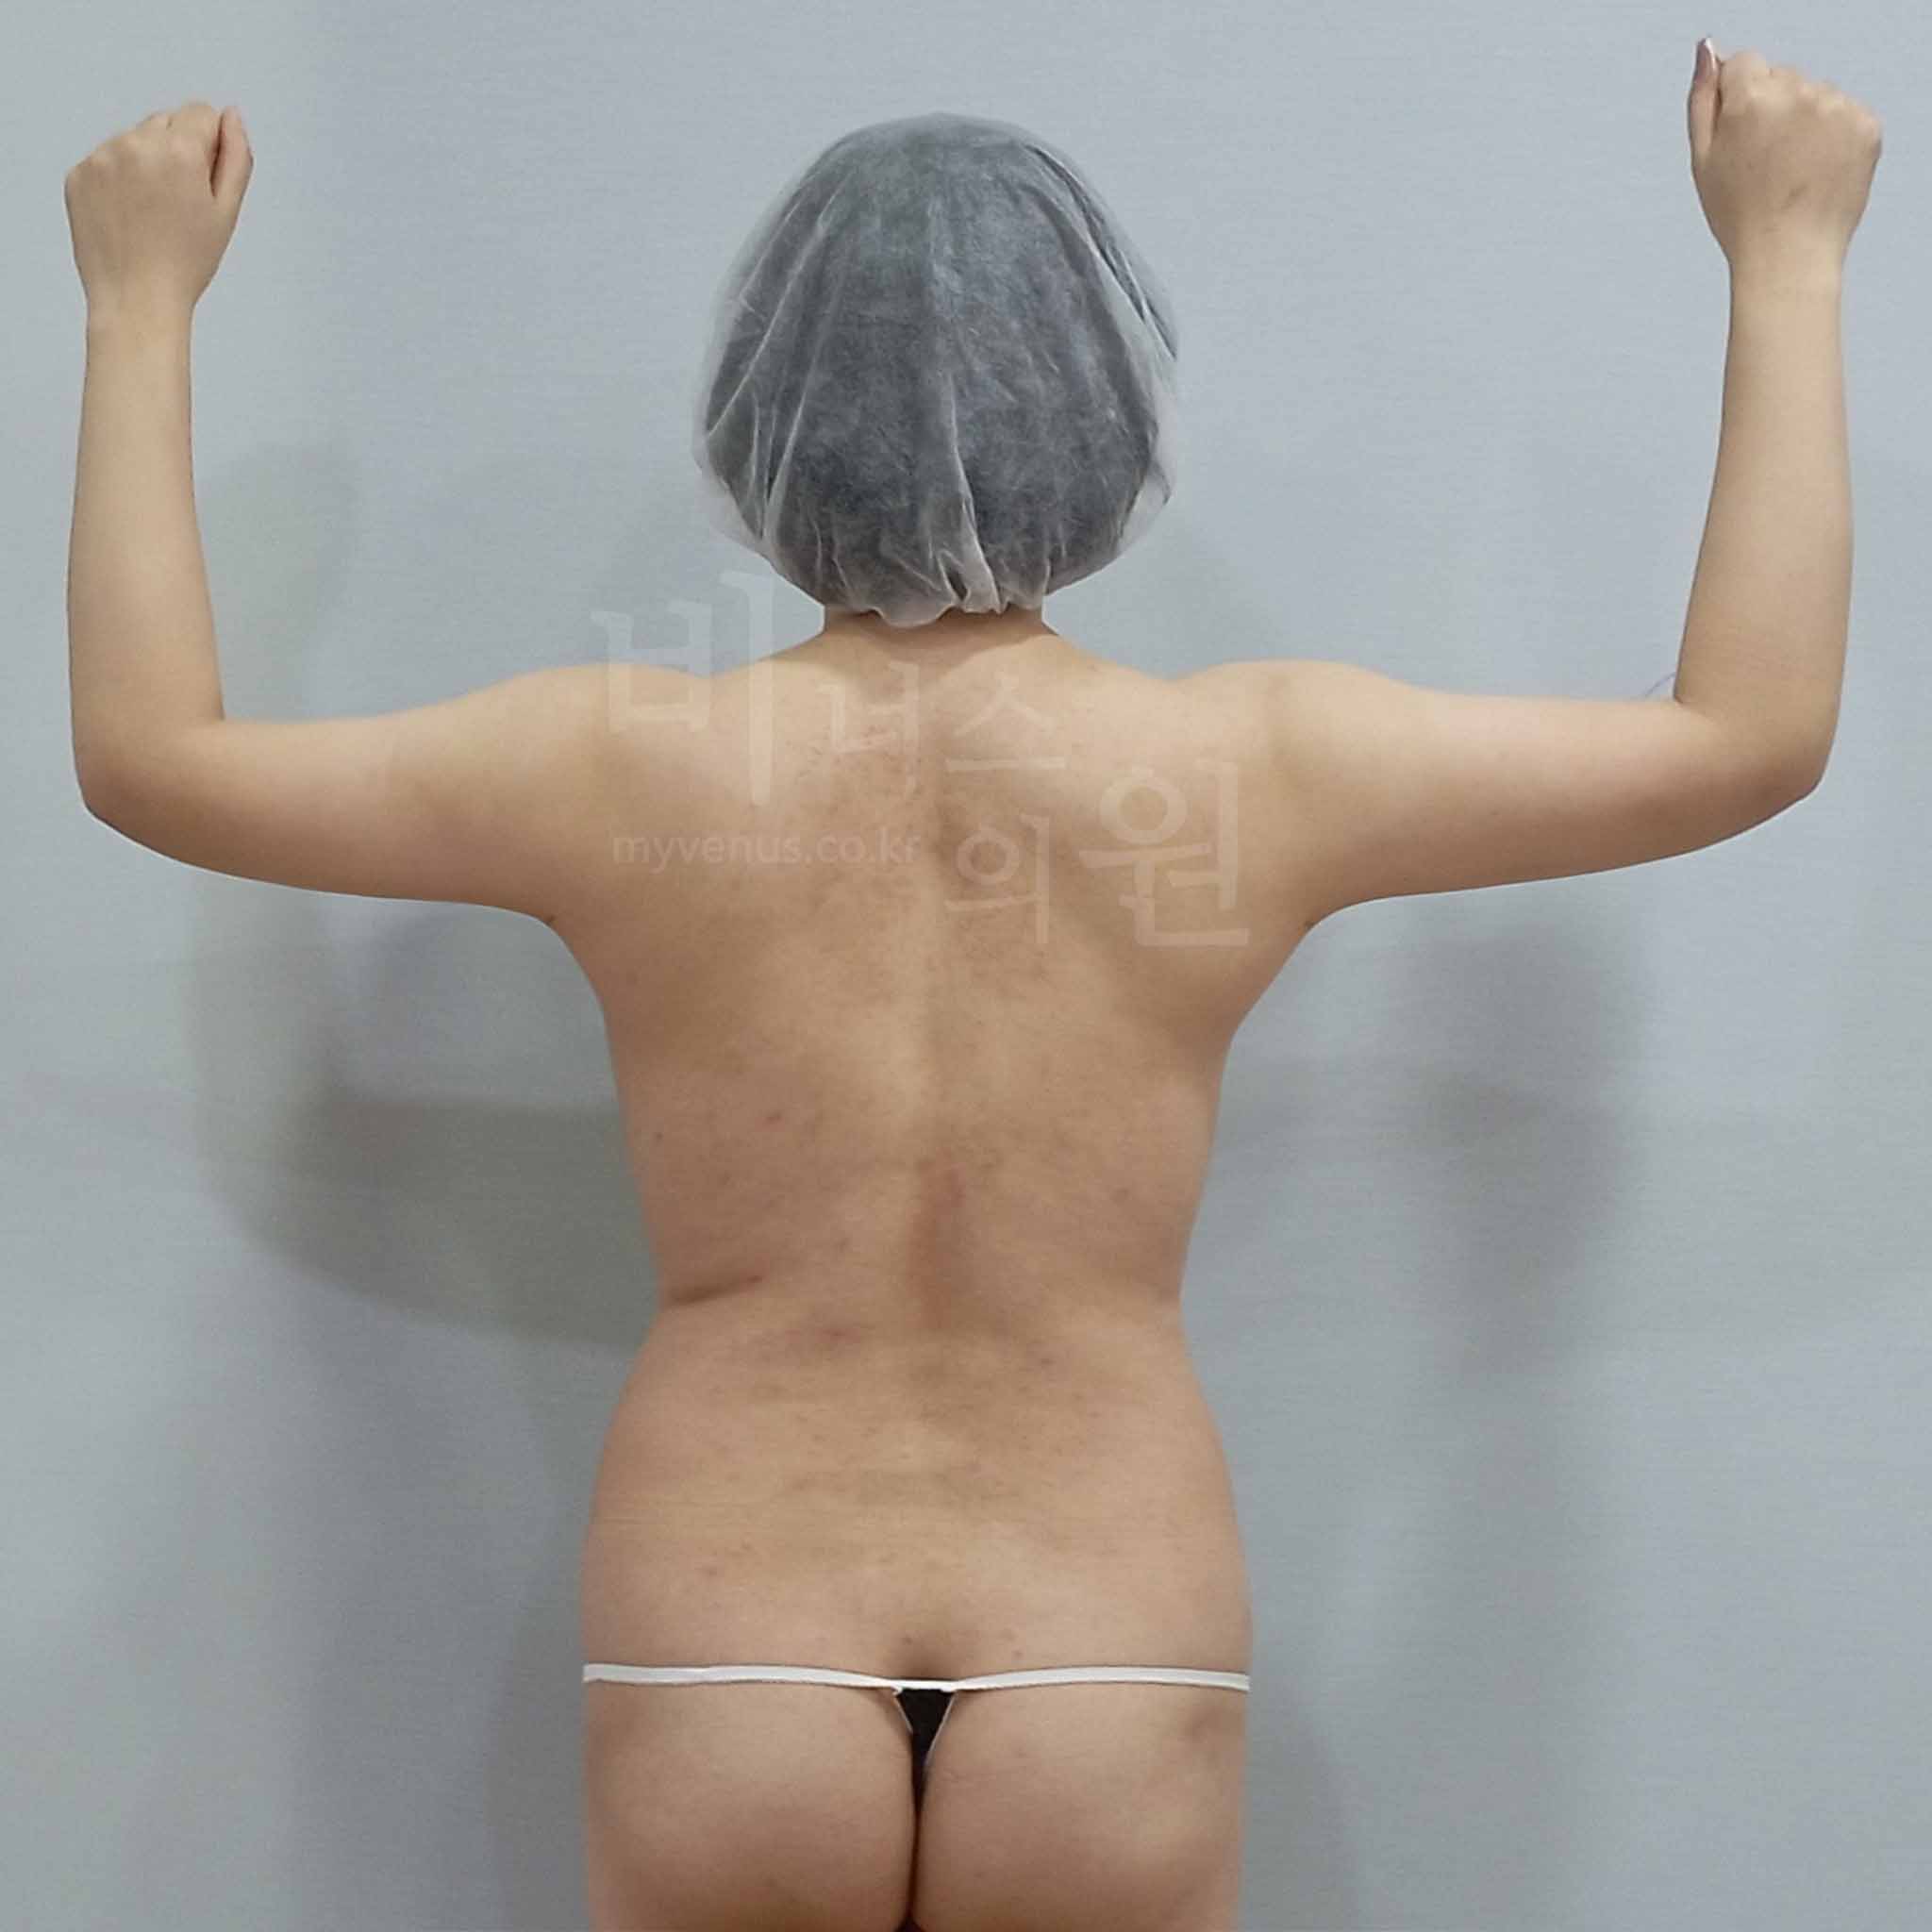

수술 전 - 차렷 자세에서도 넓고 퍼져 보이는 팔뚝살로 인해 덩치가 있어 보이고, 상체 전체가 더 커 보이는 체형으로 스트레스를 겪으셨습니다.

수술 후 - 360도 원통형 팔뚝 지방을 정교하게 제거해 팔뚝 라인이 매끄럽고 직선적으로 정리되었습니다. 팔뚝 부피가 줄어들면서 상체 뒷모습까지 슬림하게 개선되었고, 덩치 있어 보이던 인상이 여성스럽고 가벼워진 느낌으로 변화했습니다.

수술 전 - 전체적으로 볼륨감 있고 퍼져 보이는 팔뚝 라인과 함께 뒷겨드랑이 주변의 군살로 인해 브라라인 위로 살이 튀어나와 상체 실루엣이 무겁고 정돈되지 않은 인상을 주셨습니다.

수술 후 - 균일한 형태로 팔뚝 전체 사이즈가 감소되었고, 뒷겨드랑이 지방흡입을 통해 브라라인 상방의 군살까지 개선이 되었습니다. 팔뚝에서 이어지는 뒷모습의 실루엣까지 자연스럽게 개선되었습니다.

연령대 - 50대 중반

경과 기간 - 일주일 경과

수술 부위 - 팔꿈치 포함 원통형 팔뚝, 앞 겨드랑이, 뒷 겨드랑이, 부유방 지방흡입